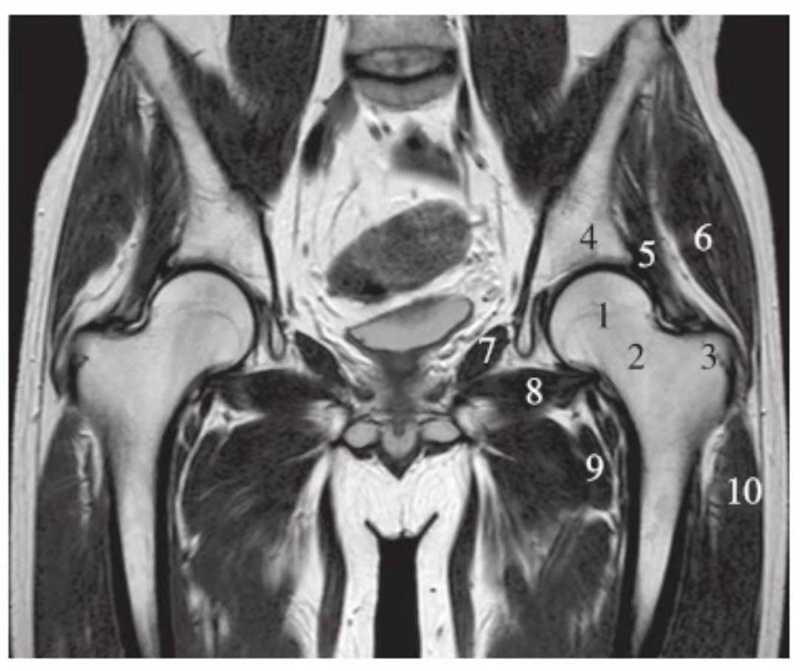

冠状位

正常髋关节经股骨头前缘层面T1WI像

1.股骨头;2.耻骨;3.髂骨;4.髂腰肌;5.内收肌群;6.臀小肌;7.臀中肌;8.关节囊及髂股韧带

正常髋关节经股骨头中心层面T1WI像

1.股骨头;2.股骨颈;3.髋臼窝内脂肪;4.髂骨;5.臀小肌;6.臀中肌;7.闭孔内肌;8.闭孔外肌;9.股外侧肌;10.股内侧肌